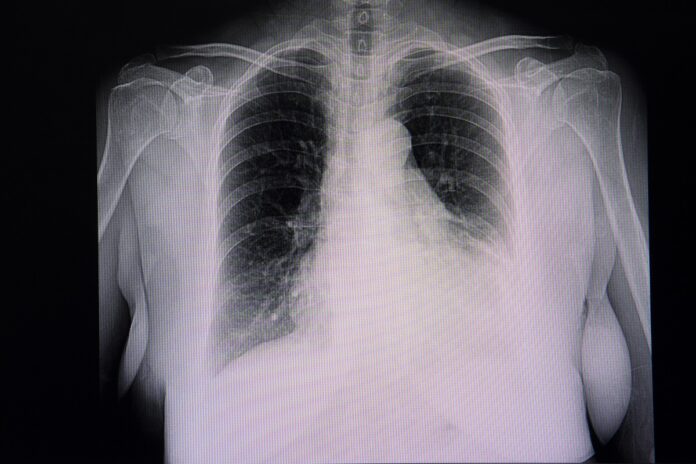

- Radiographie thoracique de face : elle suffit lors des gros épanchements.